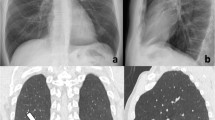

CXRs show the same temporal evolution as described on HRCT, with a progressive increase of confluent alveolar opacities having a typical predominant peripheral distribution, bilaterally [22, 23] (Fig. 3).

Bedside chest radiograms of a patient with a severe condition of COVID-19 pneumonia showing the temporal lung changes from the early phase (a), characterized by bilateral interstitial opacities with peripheral mid-lower lung distribution, to the peak phase (b) with bilateral and more extensive confluent alveolar opacities. Note the presence of endotracheal tube and central venous catheter in both radiographs

In patients developing an ARDS (up to 40% of COVID-19 pneumonia cases, 20% of whom experiencing a severe form) [44], lung involvement is usually diffuse, and massive bilateral alveolar opacities and consolidation can be seen on CXR and HRCT respectively (“white lung” appearance) [45].